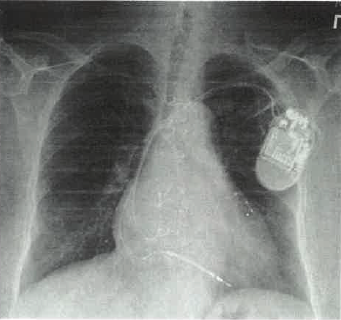

Beginning in 2005, that unhappy family history caught up with Terry, requiring bypass surgery and, later, an implanted defibrillator. Over the years, her heart weakened further.

“Terry had developed congestive heart failure,” Dr. Choudhuri said, “requiring that I replace her defibrillator with a special defibrillator that re-coordinates the way both sides of the heart beat. She was feeling better within days – even able to exercise again.: